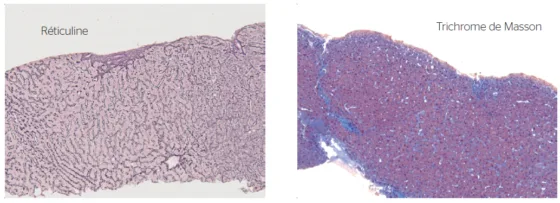

Les causes d’hypertension portale non cirrhotique en fonction de la localisation du bloc pré-sinusoïdal, sinusoïdal ou post-sinusoïdal sont résumées dans le tableau 3. Les complications de l’hypertension portale non cirrhotique sont dominées par les hémorragies digestives par rupture de varices alors que l’ascite n’est présente que dans 10 à 34 % des cas [13-14]. Le diagnostic est porté par l’étude hémodynamique et surtout par la biopsie hépatique. Le diagnostic anatomopathologique est souvent difficile et nécessite un prélèvement de taille suffisante [15]. Le dialogue avec l’anatomopathologiste est très important et permet de préciser l’atteinte vasculaire et la présence éventuelle d’une hyperplasie nodulaire régénérative avec transformation nodulaire du parenchyme hépatique en l’absence de fibrose extensive péri-nodulaire (Fig. 4).

d’une hépatite granulomateuse

révélant une sarcoïdose

Dans certains cas, le diagnostic de la cause de l’hypertension portale non cirrhotique peut être très difficile ou révéler une pathologie inattendue (Fig. 5).